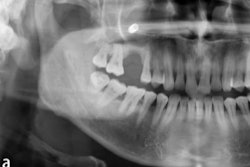

"Jack went through a traumatic injury to his front teeth today amid his win," Dr. Auerbach said on Sunday. "He will need an evaluation and closure of any soft-tissue injuries that likely occurred. Once he is stabilized, he will need imaging to determine the extent of dental and bony injuries. He will probably require removal of some teeth in full and bone grafting versus endodontic treatment."